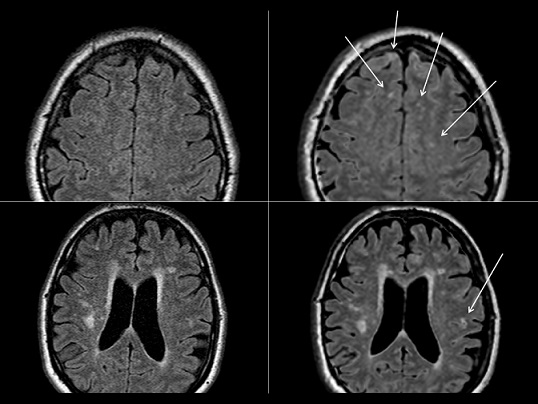

Synthetic images are obtained from a single acquisition – with mathematical reconstruction of T1 and T2 – like images. A comparison with “native” images shows that it is a good alternative in patients with multiple sclerosis (MS).

Article: Conventional and synthetic MRI in multiple sclerosis: a comparative study